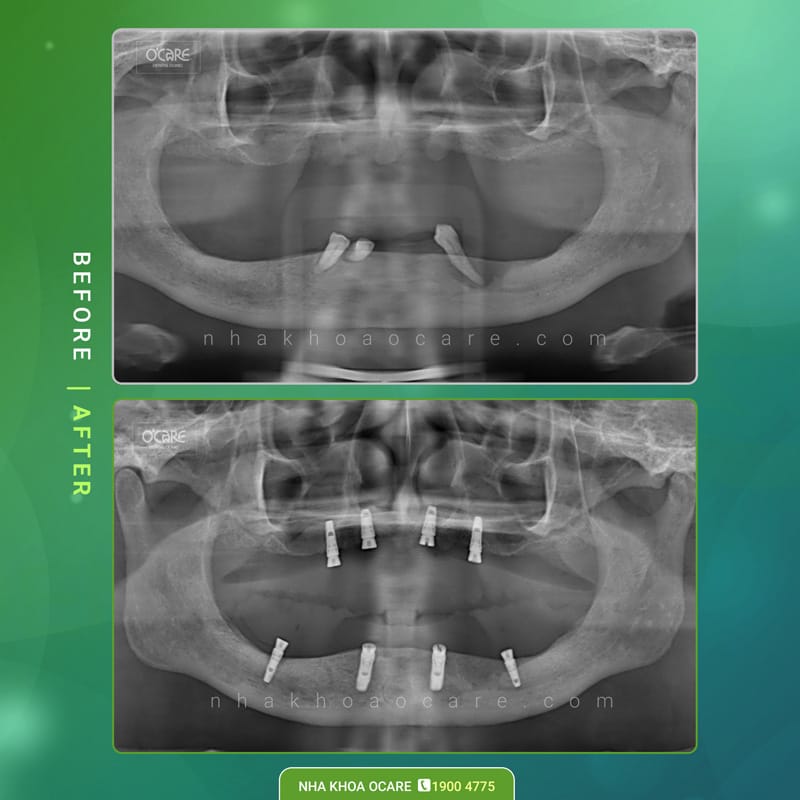

Thực tế, chi phí Implant không có mức cố định mà sẽ phụ thuộc vào nhiều yếu tố như loại trụ, tình trạng xương hàm và kế hoạch điều trị của từng bệnh nhân.